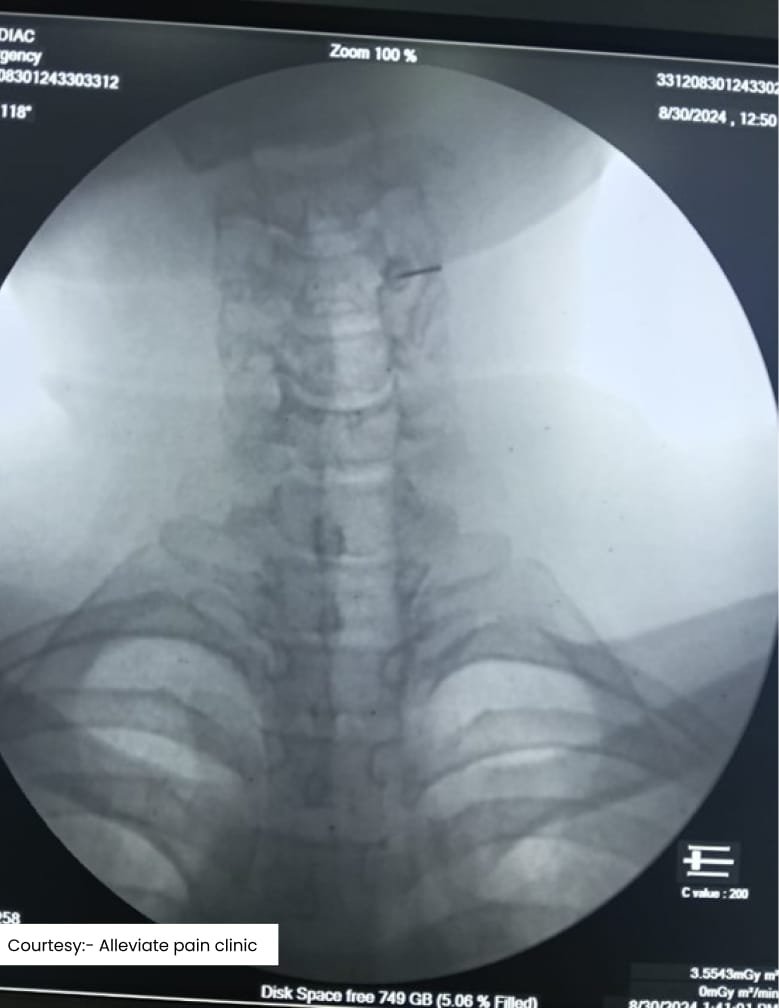

Scan2

Scan3

Fluoroscopic guided medial branch block for cervical facet joint syndrome sone at Alleviate Pain Clinic

Each of these procedures is performed using image guidance—such as fluoroscopy or ultrasound—to ensure precise needle placement and maximum effectiveness. This approach minimizes complications and maximizes pain relief.